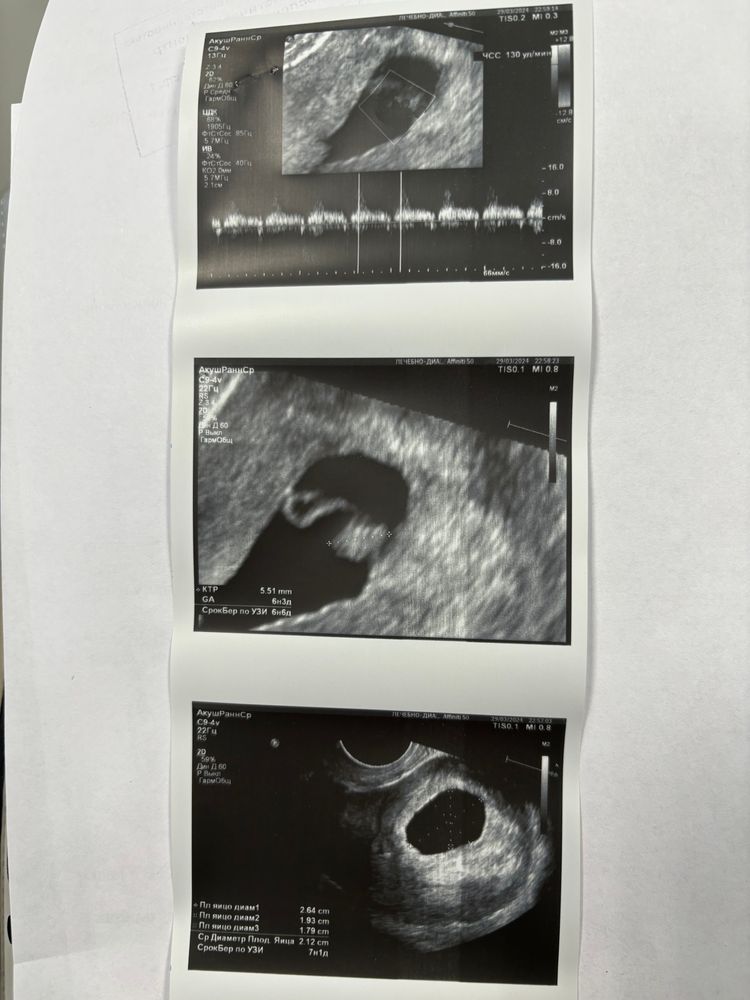

Не дождалась я своего назначенного приема на 5 марта и решила сходить на УЗИ, чтобы удостовериться, что с малышочком все хорошо, так как выделения все еще есть, но уже ближе к бежеватому цвету и не такие обильные. Ну и конечно же со сдачей крови для репродуктолога заодно решила и ХГЧ сдать для себя… больно нравятся мне эти большие цифры 😄 Итог ХГЧ на 28дпп 138 687 😊

По узи тоже сказали все хорошо, никаких отслоек и гематом нет, так никто и не нашел причину кровотечения и дальнейших выделений, начиная с 19дпп.

ну и главные показания следуюшие: ПЯ 21мм, КТР 5,5мм, ЖМ 5мм, ЧСС 150 уд/мин 😍

но теперь задумалась, что ПЯ за неделю не сильно подросло 🤔 на 21дпп оно было 18мм, а сейчас 21мм, но может из-за того, что в другом месте делала и аппараты разные 🤷♀️